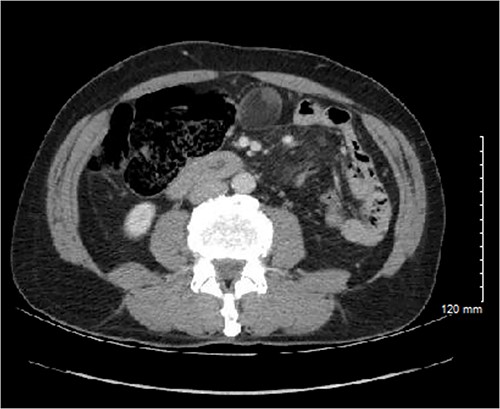

Therefore, the patient underwent planned, hand-assisted laparoscopic resection of the cecal mass and appendectomy. At the time of surgery, the abdomen was accessed laparoscopically, and the mass was revealed in the pelvis after mobilization of the omentum and small bowel. The mass itself was soft and appeared to arise directly from the lateral wall of the cecum as it transitioned into the right colon (Fig. 3). It was clearly distinct from both the terminal ileum and appendix. The mass was eviscerated through an infraumbilical incision, and a partial cecetomy and appendectomy en bloc with the mass was performed.